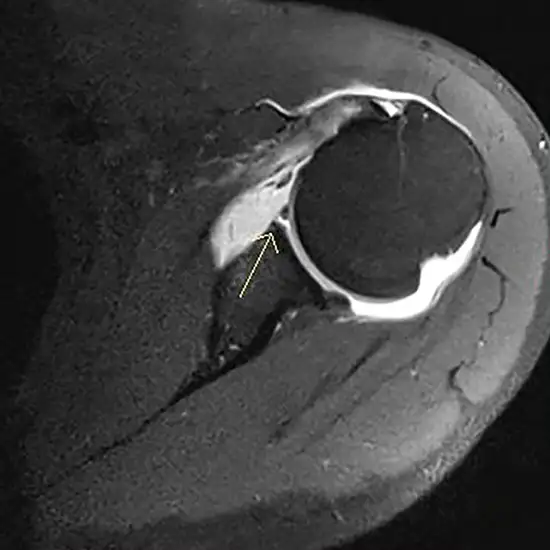

An arthrogram is a diagnostic tool medical professionals use to identify joint disorders, such as hip or shoulder pain. MR arthrograms can reveal ligament, tendon, and cartilage abnormalities in exquisite detail. A specific dye is injected into your joint before undergoing an MRI or other imaging procedure.

Arthrograms assess the joint tissues of the body. Typically, this technique is performed to evaluate your shoulder (called a shoulder arthrogram) or hip (hip arthrogram).